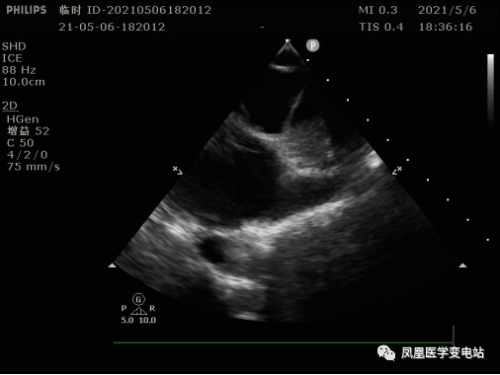

为防止术中出现卒中的可能,同时需术前评估左心耳及左心房的情况,必须搞清楚房颤患者心房是否出现血栓,食道超声检查显得十分必要。可该患者却无法耐受食道超声。刘燕锋向患者及家属建议,只能选择在术中使用超声导管,通过超声导管,一可以检查病人左心耳及左心房有无血栓;二可以指导房间隔的穿刺,由于右位心患者与正常人不同,使用超声导管协助手术可以降低手术难度,保证手术安全;三是术中可以实时监测心包有无积液。

术中心包监测

术中左房手术模型